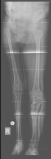

ORTHO-SUV FRAME – is a new generation computer assisted external fixation device. Ortho-SUV Frame is an advanced extension of traditional Ring Fixator developed in Russia as a single step solution for treating complex deformities and fractures. It reduces the time for deformity correction. The main advantage of SUV is the perfection of correction in deformity correction. It corrects the deformity in all plane.

Wide range of indications:

• Two level bone deformities Complex foot deformities

• Long bones deformities of any complexity

• Severe contractures and old subluxations of large joints

• Extra articular fractures of long bones

• Single stage correction for Multi Planar Deformity & Fracture Reduction

With traditional method of ilizarov deformity correction, it is a time consuming procedure and patient needs to attend the doctor so many times. Here the patient himself can correct the deformity by rotating the struts on the SUV .once the deformity corrected then the SUV can be removed and normal hinge joint can be connected./p>